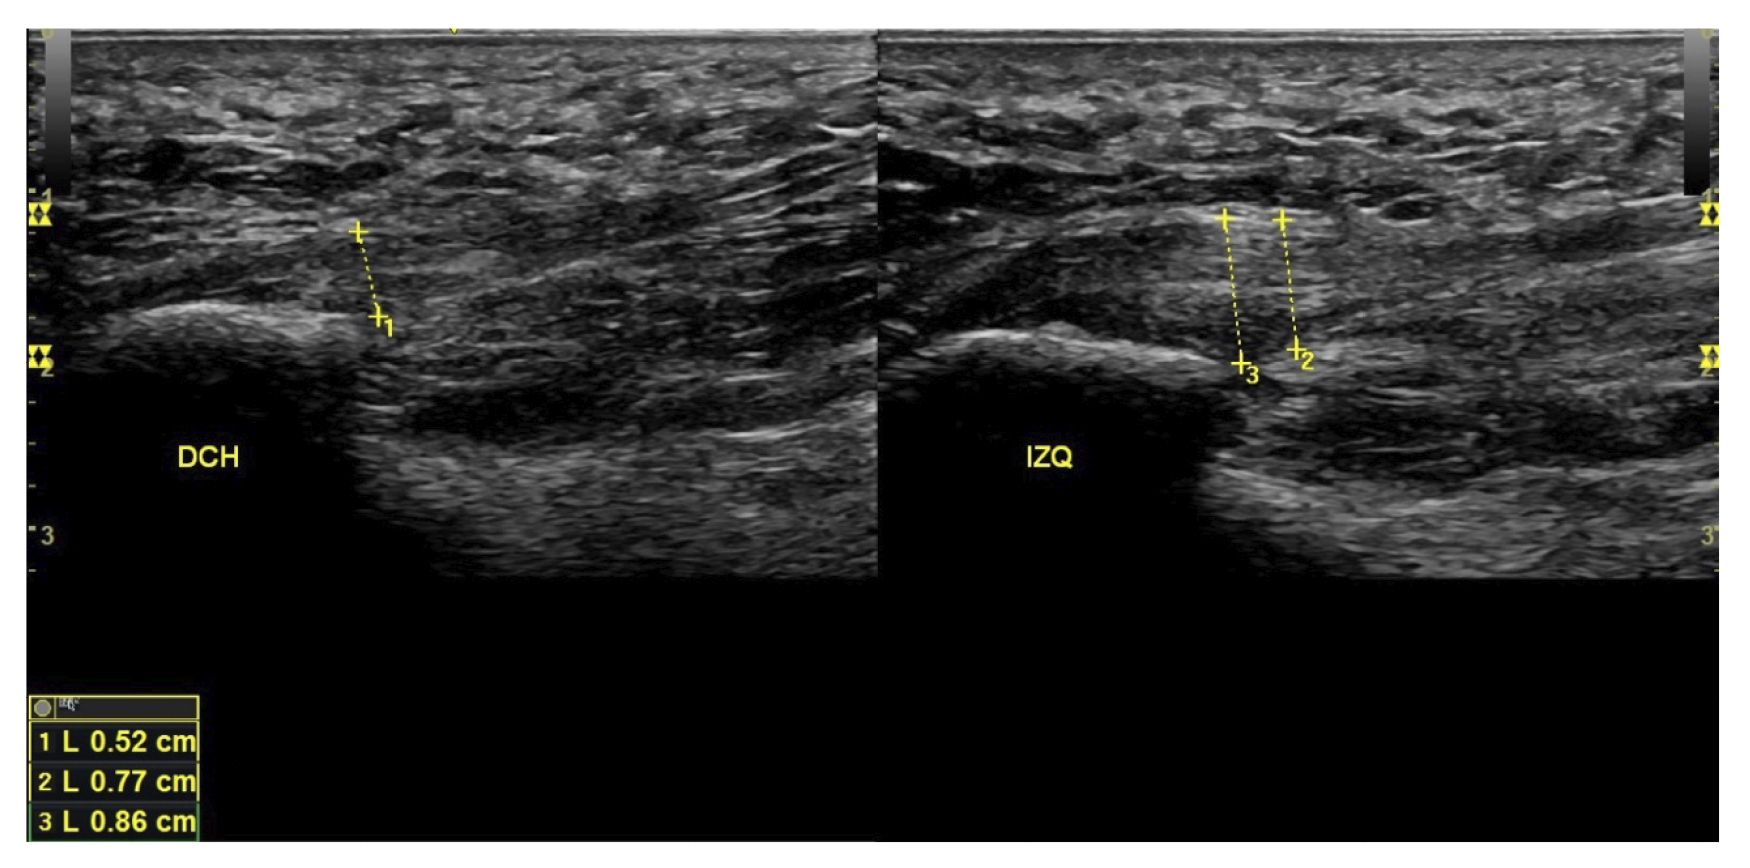

A todos los pacientes se les realizó una evaluación clínica y una evaluación ecográfica. La evaluación clínica se basó en una escala analógica visual (EVA) (13) (0-10) y el índice de función del pie (FFI) (14,15), que evalúa la función en una escala de 0 a 100. También se clasificó a los sujetos como sedentarios, activos o deportistas en función a su actividad física diaria, así como si era la primera vez que aparecía la enfermedad, era una recidiva o era crónica(16). También se evaluó el sexo, el peso y la talla, la presencia de vascularización en la fascia plantar visualizada con ecografía en el momento de la evaluación inicial y la forma biconvexa(17) o aplanada de la fascia plantar (Figura 1).

El diagnóstico se estableció en base a los síntomas y se confirmó mediante ecografía con equipo de alta resolución (Alpinion Ecube 9, ALPINION MEDICAL SYSTEMS Co., Ltd., República de Korea) con transductor lineal de 6 a 12 MHz (Figuras 2 y 3).

Figura 2. Investigador con la sonda lineal para la medición del grosor de la fascia plantar.

Figura 3. Área de medición del grosor de la fascia plantar. La línea punteada corresponde con la medición del grosor.